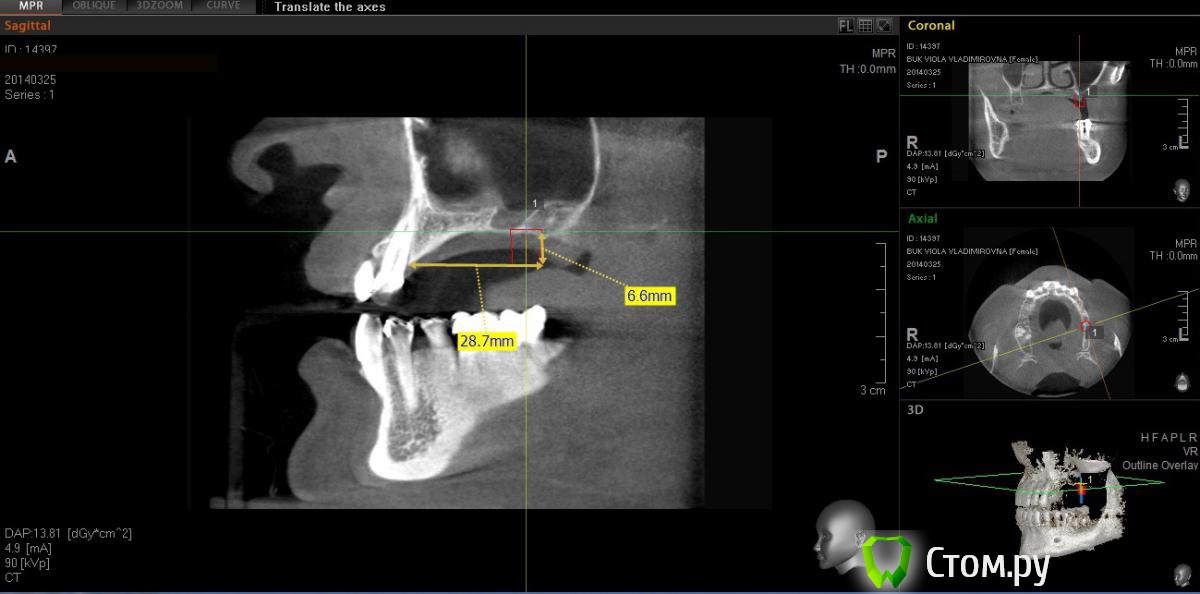

diesel87 Опубликовано 22 июня, 2014 Поделиться Опубликовано 22 июня, 2014 Планирую вертикальную аугментацию, синус с ксено, ауто с нижней челюсти под Цитопласт, дистально ограничив его цилиндром взятым трепаном с нижней челюсти, поставить цилиндр дистально, накинуть окклюзионно на него цитопласт и привинтить вертикально, образовавшееся пространство забить ауто+ксено. Что скажите? Ссылка на комментарий

АнтонТЛТ Опубликовано 22 июня, 2014 Поделиться Опубликовано 22 июня, 2014 (изменено) Выложи ОПТГ, на ней будет понятнее нужно ли вертикалить Как мне кажется ниче там не нужно кроме синуса.Ну или выстави срез, чтобы попадал дистальный край альвеолярного отростка Изменено 22 июня, 2014 пользователем АнтонТЛТ Ссылка на комментарий

diesel87 Опубликовано 22 июня, 2014 Автор Поделиться Опубликовано 22 июня, 2014 Понимаю что можно не вертикалить, коронки получатся тогда огромные, есть возможность показать как выглядят такие коронки на оптг и на фото во рту? Ссылка на комментарий